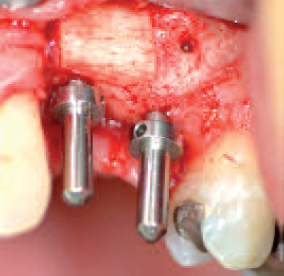

Presentation of bone defect (above all horizontally) after implant drilling in region 12

Inserted guide elements after removal of the osteosynthesis materials four months post operationem

nserted implant with buccal bone defect at the level of the implant shoulder